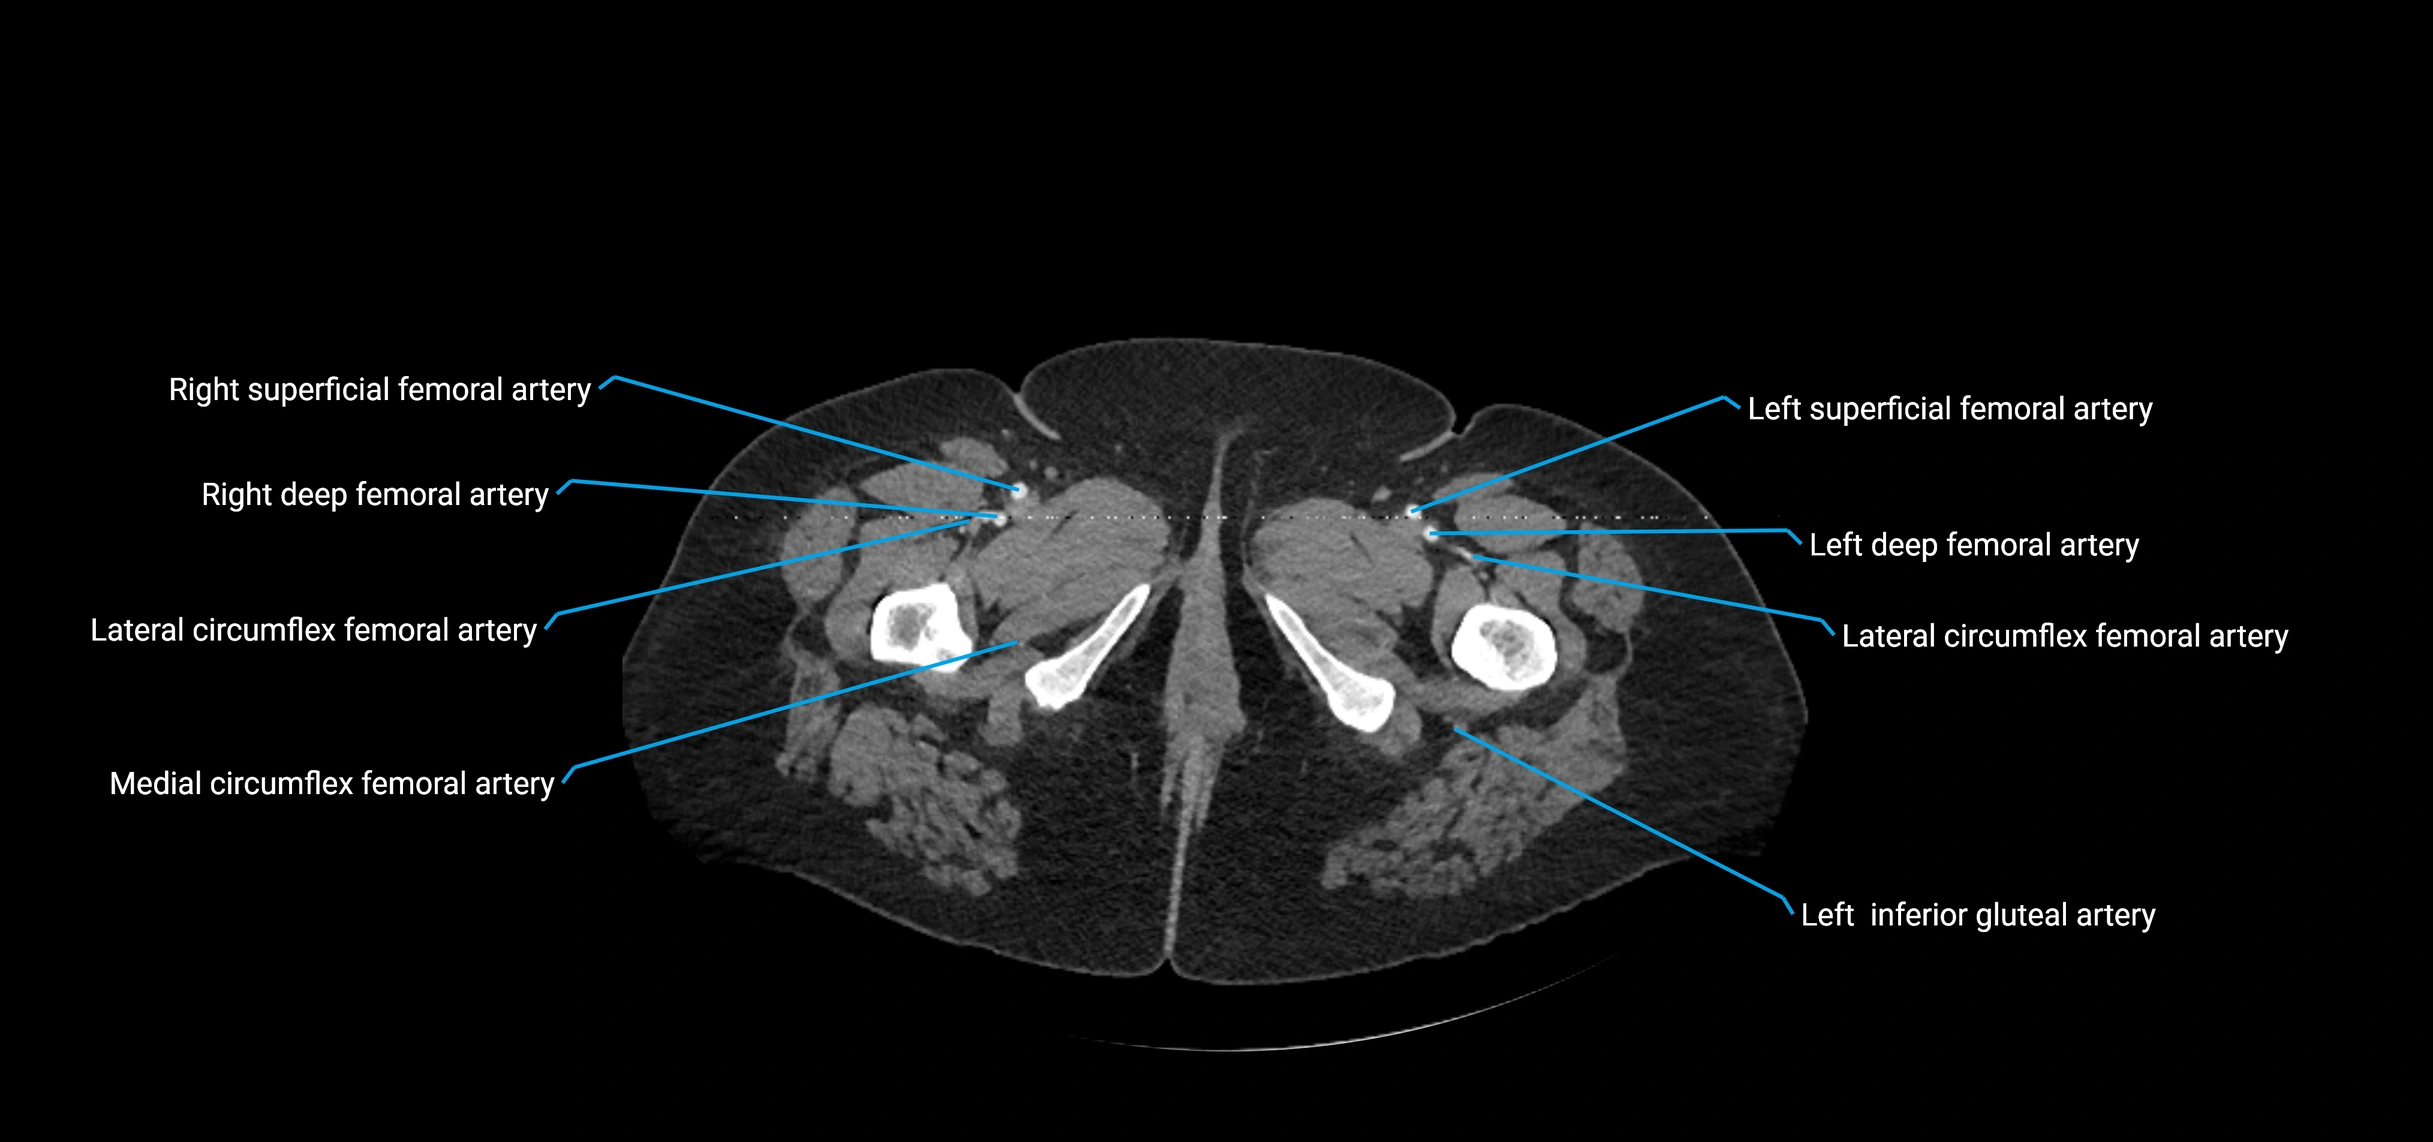

Contrast-enhanced CT (CTA):

• Gold standard for abdominal aortic imaging

• Provides excellent detail of lumen, wall, aneurysm, thrombus, and branch vessels

• Multiplanar and 3D reconstructions help in aneurysm measurement, stent graft planning, and dissection evaluation

• Detects acute rupture, traumatic injury, or occlusion with high sensitivity